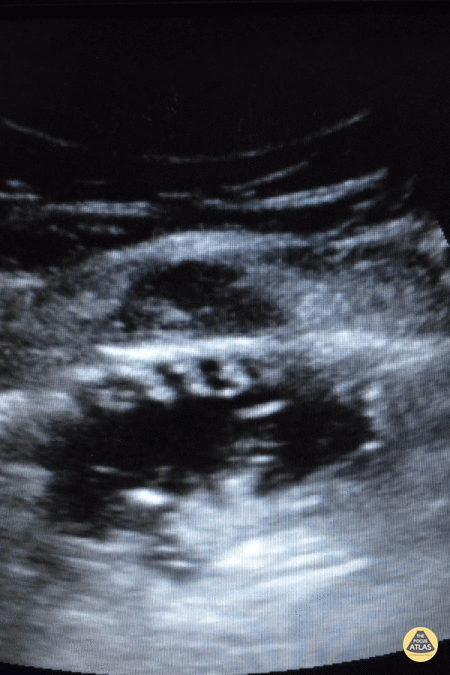

Bowel-GI - The Piano Sign

A 55 year old male came to ED c/o abdomen pain for 3 days associated with abdominal distention and vomiting. He was noted to be tachycardic and his abdominal exam demonstrated tenderness and bulging in the right inguinal area. A curvilinear probe was used to evaluate for bowel obstruction. The clip demonstrates a dilated loop of bowel, "to and fro" movements of bowel content suggesting dysfunctional peristalsis, and the piano sign. The piano sign (or keyboard sign) is essentially visualization of the plicae circularis which is associated with the diagnosis of small bowel obstruction. Dr. Mahmoud S Alsomali EM Resident R4; Saudi Board Of Emergency Medicine; King Saud Medical City; Riyadh KSA